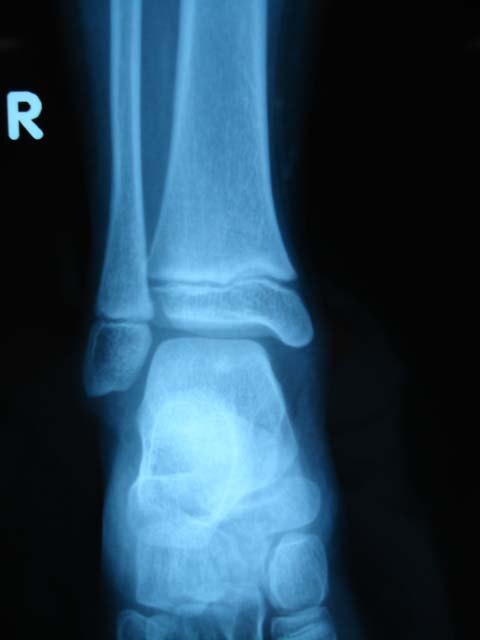

女,9岁。下楼是扭伤脚部。大家看看跟骨骨骺正常吗?有疲劳性骨折么?其骨化中心只有1个吗?

未见异常,跟骨化骨中心有-----两个。

正常,正常跟骨骨骺骨化中心可\"节裂\",密度较高

支持两个骨化中心。

两个骨化中心

无异常.儿童骨骼摄影必要时可摄双侧对比

支持跟骨两个骨化中心     边缘较光滑      必要时可摄片双侧对比